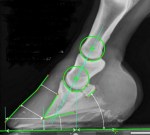

Om man istället tar en röntgenbild kan det se ut som om hovbenet roterat inne i hovkapseln, eftersom man oftast inte ser att lamellerna har tänjts sönder och bildat en lamellkil på en röntgenbild.

Vid diagnosen hovbensrotation mäter veterinären vinkeln på hovväggens främre yta och vinkeln på hovbenets främre yta utifrån röntgenbilden.

När ytskiktet på hovväggen och främre ytan på hovbenet inte är parallella kallar veterinären fenomenet “hovbensrotation”.

Skillnaden i grader beskriver hur stor “rotation” som skett.

Man ser tydligt på röntgenbilderna att hovväggen faktiskt är tjockare/mer uttänjd ju mer “rotation” som finns, fast man kan inte på röntgen urskilja stretchad lamell eller områden med stelnad sårvätska.

Man ser också att trakten är högre ju mer “rotation” hoven har. Det vill säga att hovbenet börjar tippa framåt med för hög trakt.